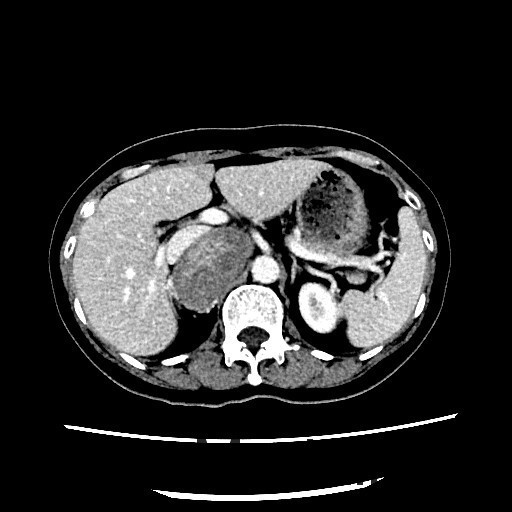

查体:血压:152/80mmHg。双肾区无红肿、隆起,双肾区叩击痛(-),双侧肋脊点、肋腰点压痛(-)。 辅查:CT平扫+增强扫描示:右侧膈下肾上腺区和左侧腰大肌病灶, 考虑为良性肿瘤,嗜铬细胞瘤可能性大,未除外其他

随访:病理回报示:嗜铬细胞瘤。 讨论:该例嗜铬细胞瘤具有较典型的影像表现,我们能看到右侧肾上腺椭圆形肿块,边界清楚,直径较大,这可区别于肾上腺腺瘤,后者一般小于2cm。增强扫描肿块明显强化,并可见无强化低密度区,可能是肿瘤常坏死或陈旧性出血引起。而且该患者有嗜铬细胞瘤引起的继发性高血压,不过追问病史没有典型的阵发性高血压发作。